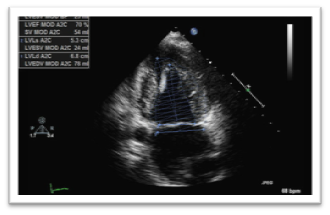

A complete 2D TTE study was performed in all subjects, using a Philips iE33 xMATRIX (USA) equipped with x5 transducer. All acquisitions were performed by same operator with subject in left lateral position. LVOT diameter measurements had an image recorded in 2D parasternal long-axis view with zoom mode activated. The gains were adjusted to optimize the blood tissue interface. The measure was made inner edge to inner edge, in mid-systole, parallel and adjacent to the aortic valve or at the site of velocity measurement. About LVOT VTI, the image was recorded with pulsed-wave Doppler in five-chamber view by placing the sample volume of PW Doppler at the base of the aortic leaflets. The proper time axis was bigger than 100 mm/s in order to obtain a better delineation, with low wall filter setting and adjustment of baseline and scale to maximize the size of velocity curve. VTI was traced.14,15 Apical two-chamber and four-chamber view were recorded for assessment of EF by Simpson’s biplane method. Matrix-array transducer was used for the acquisition of the 3DE data sets from four consecutive cardiac cycles during end expiration breath-hold in apical view (Figures 14).

Figure 1 Simpson’s Method by two-dimensional echocardiography in four chamber apical view.